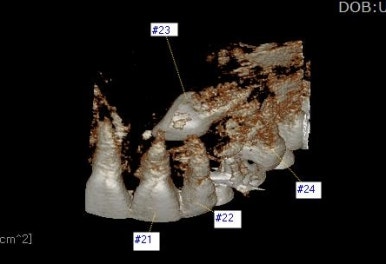

부산매복치아교정 키다리아저씨치과에서 촬영한 3D CT를 입체사진으로 재구성해보면 훨씬 직관적으로 눈에 띄게 위치를 판단할 수 있게 해줍니다.

위치를 정확하게 파악하는 것이 중요한데 결국은 잇몸을 째고 정확한 치아 머리를 향하여 들어가서 장치를 부착해야 되기 때문이죠.